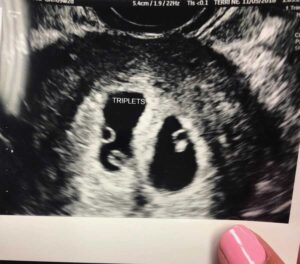

Monday morning, November 5, rolled around and I was about to have my first ultrasound. The ultrasound tech began her exam when she said, ‘Oh do you see what I see?’ My response was, ‘Oh no, two sacks, don’t tell me we are having twins?’ The tech then said, ‘No, no, count the eggs…’

Okay, in my head I begin to count. One, two… (losing it a bit), and yelled out, ‘OHHHH MY GOODNESS IS THAT THREE EGGS!’ The tech responds by saying, ‘That’s right, you’re carrying TRIPLETS.’ Now if you can imagine my reaction, I was laying on the ultrasound chair crying hysterically, turning all shades of white while my husband, who was carrying our 9-month-old daughter, was crying in happy tears. The ultrasound tech of course asked, ‘Oh were you on any fertility treatment?’ I said, ‘No, this was completely natural.’ She said, ‘WOW!! YOU HAVE SPONTANEOUS TRIPLETS, This is a 1 in 10,000 type case you have here.’

I left that ultrasound to meet with the OB. The OB informed me I was only 6 weeks along and there was a high probability I may lose one or all three. ‘Don’t stress it’ DON’T STRESS IT! Is he out of his mind? I could only think, ‘Five kids, five kids, OMG how am I going to afford five kids. We went home and I curled in bed and just cried, cried, and cried some more. I wish I could say I took the news better, but I didn’t. I spent the next 4 weeks crying and going through all the emotions of depression, anxiety, and fear while I waited to see if we, in fact, lost a baby or not. Appointment day arrived and I completed another ultrasound. This time, all three babies were thriving, and heartbeats were well over 120 bpm. The OB kindly suggested I look into having a fetal reduction procedure. I can’t say it wasn’t in the back of my head, but how could I possibly reduce my pregnancy?